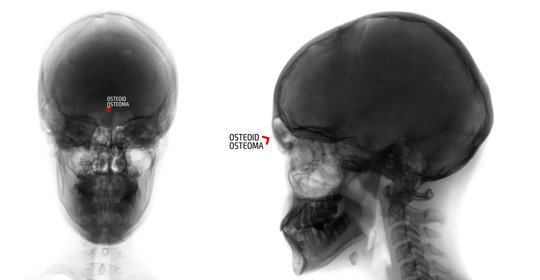

X光檢查

透過拍攝面部正側位片可以觀察到顴骨的位置、形態是否正常,並可與對側比較以評估其對稱性。患者需要坐於特製椅子上,按照指示調整頭部位置後進行拍攝。